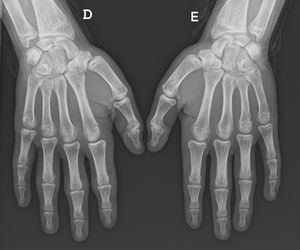

A previously healthy boy aged 14 years presented with painless, well-circumscribed swelling over the joints of the right hand with onset 1¿;year prior. The personal and family history was unremarkable. The physical examination revealed cutaneous thickening over the proximal interphalangeal and metacarpophalangeal joints (Fig. 1). There were no other signs of inflammation. The assessment of muscle strength was normal. At the time, the patient practised judo and bodybuilding regularly without limitations. He reported that the onset of the lesions was associated with an increased use of the PlayStation. Laboratory tests, including the erythrocyte sedimentation rate and the C-reactive protein level, were normal, as were the radiographs of both hands (Fig. 2). The patient was referred to a dermatologist to rule out other conditions. He started treatment with localized massages with an emollient and reduced PlayStation usage. He was reassessed annually, with progressive improvement of his lesions.